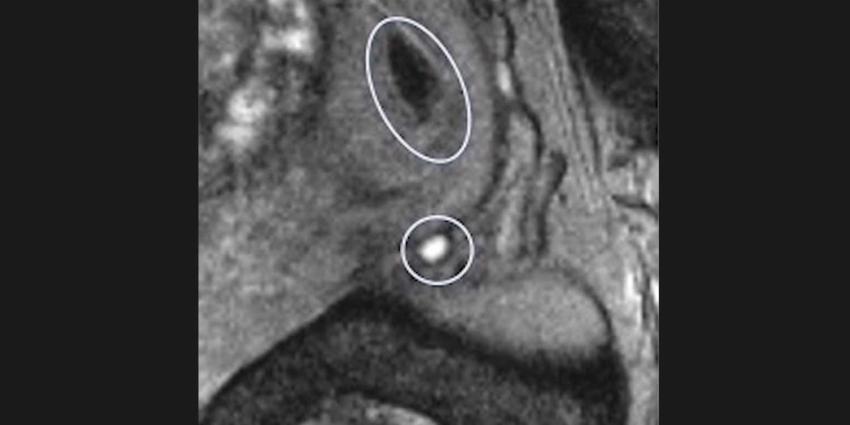

lymfeklieren